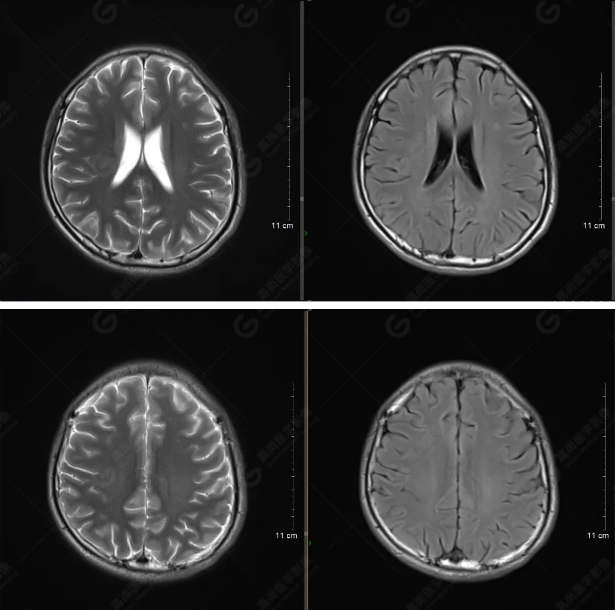

以下是平掃T2WI及FLAIR序列:

雙側(cè)大腦半球?qū)ΨQ,灰白質(zhì)對比正常,顱內(nèi)未見異常信號影。腦室系統(tǒng)未見擴(kuò)大,中線結(jié)構(gòu)居中。腦溝、裂未見增寬。幕下小腦、腦干未見異常。矢狀位示垂體形態(tài)、大小級信號未見異常。所示左側(cè)乳突內(nèi)見多發(fā)短T1長T2信號影。

顱腦MRI平掃未見明顯異常,左側(cè)乳突內(nèi)積血,建議補充SWI檢查。